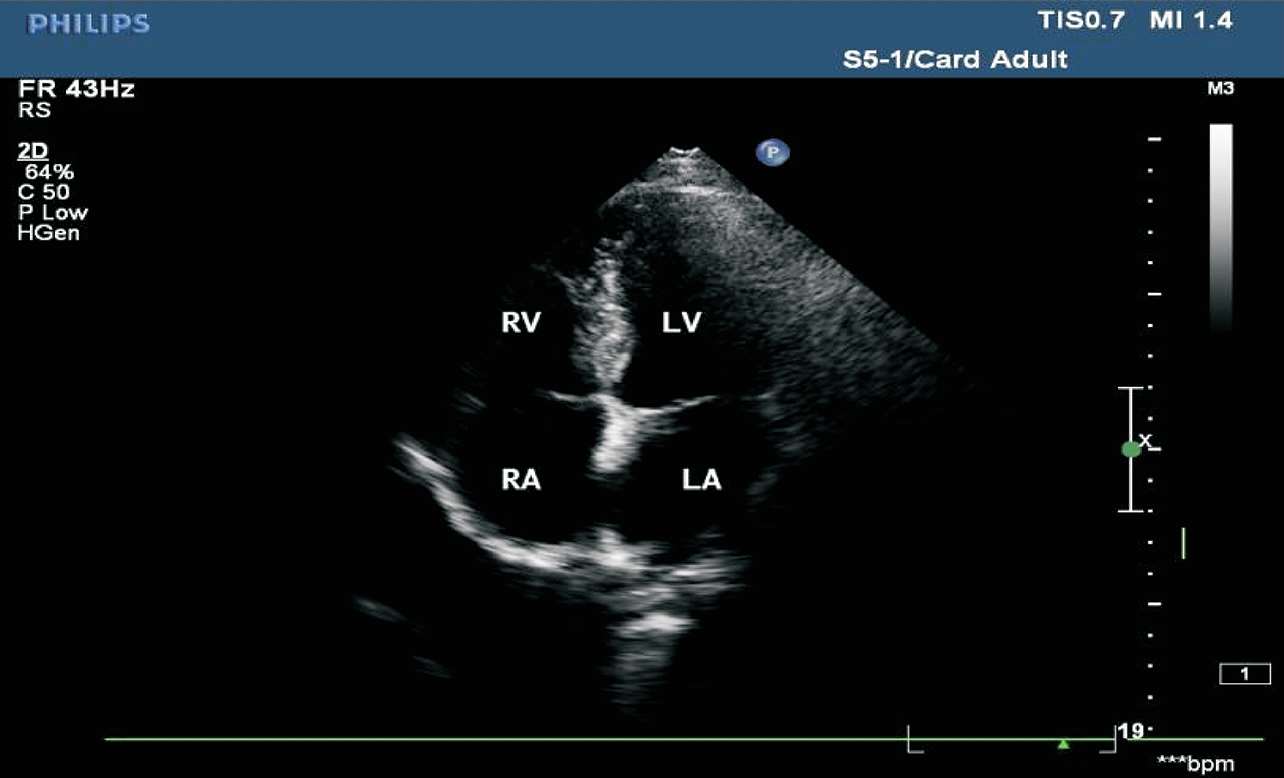

患者取平卧位或略向左倾斜,探头置于心尖搏动处,声束指向右肩胛部。在此切面可观察到四个心腔的大小、二尖瓣及三尖瓣的形态和开闭状况、房室间隔及十字交叉部结构的完整性,可评价室壁运动及心功能情况(见图1-32)。

图1-32 心尖四腔心切面(RV:右心室;RA:右心房;LV:左心室;LA:左心房)